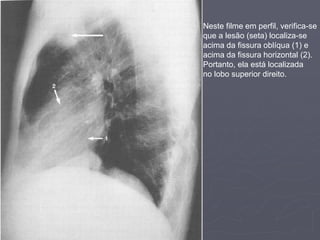

Neste filme em

PA, observa-se

que a lesão

(seta)

está localizada

acima da fissura

horizontal (1).

Neste filme em perfil, verifica-se

que a lesão (seta) localiza-se

acima da fissura oblíqua (1) e

acima da fissura horizontal (2).

Portanto, ela está localizada

no lobo superior direito.